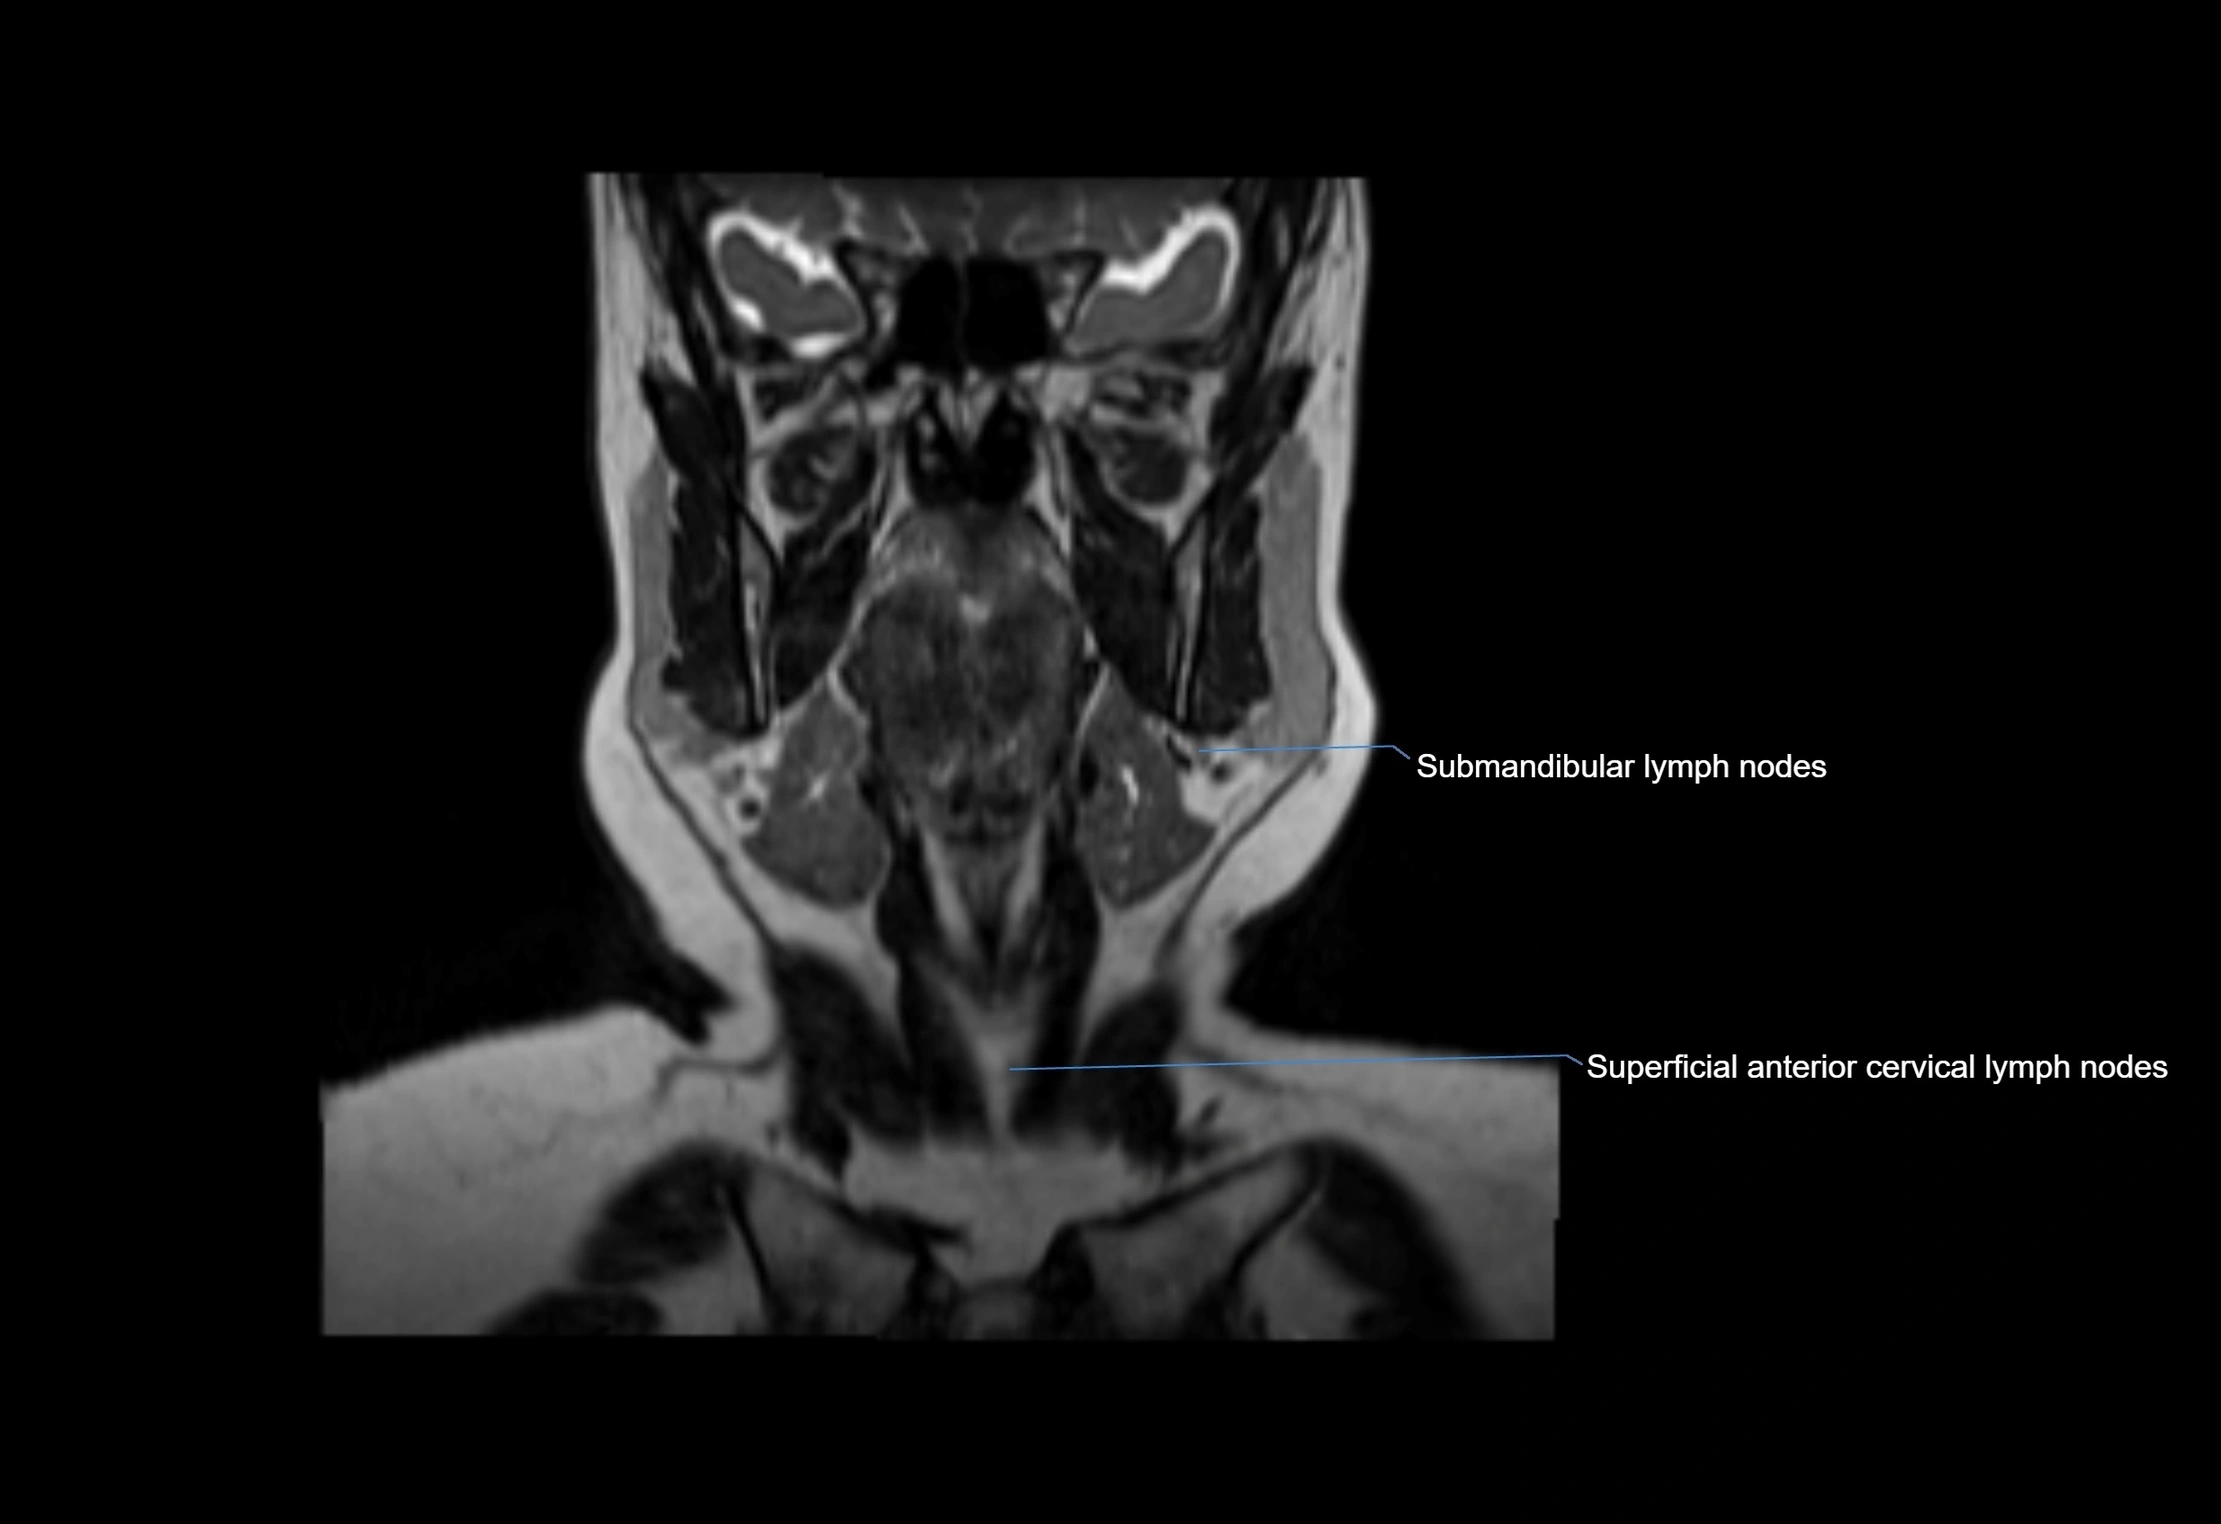

Location

• Found along primary lymph node chains, including preauricular, submandibular, parotid, and occipital regions

• Embedded in subcutaneous fat or superficial fascia, often lateral or posterior to primary nodes

• Variable in number; may occur unilaterally or bilaterally, depending on individual anatomy

MRI Appearance

T1-weighted images:

• Normal accessory nodes appear as small, oval hypointense to intermediate signal structures within subcutaneous fat

• Surrounded by hyperintense fat, enhancing contrast for visualization

• Pathological nodes may appear enlarged or rounded, sometimes with cortical thickening

T2-weighted images:

• Nodes show intermediate signal, with surrounding fat bright

• Useful for detecting edema, inflammation, or infiltration

• Fatty hilum may appear slightly hyperintense relative to cortex

MRI images

image